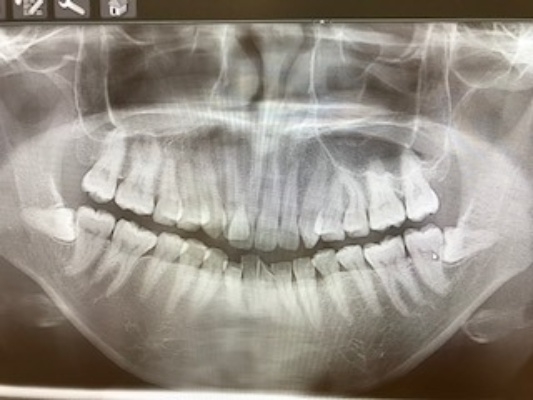

[術前パノラマレントゲン写真]

第3大臼歯を抜歯して矯正配列している症例です。